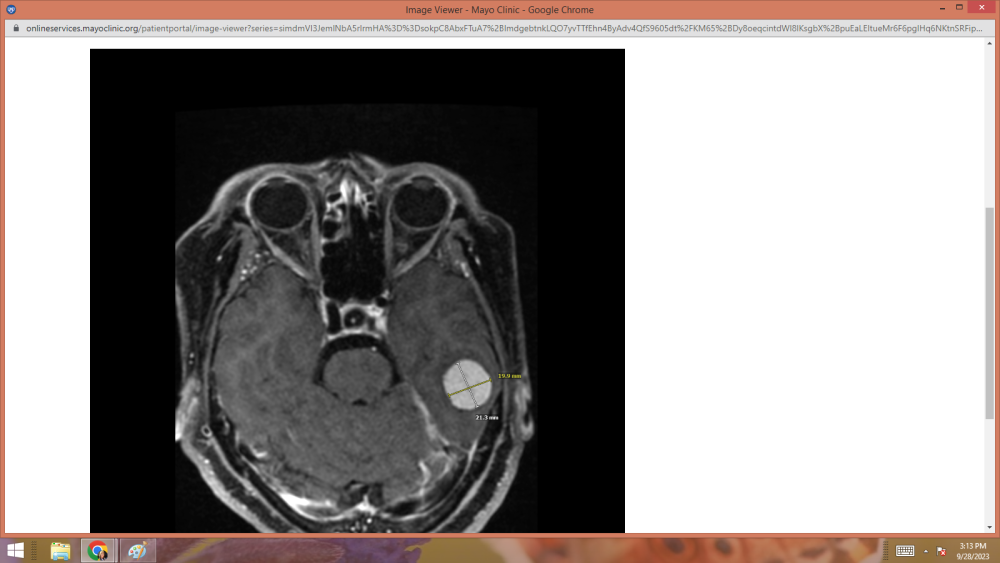

UPDATE:     GOOD NEWS!!!   My tumor hasn't grown any since 2019.

Thank you brothers and sisters for the prayers.    They were felt.

scan1.png

scan2.png

scan3.png

scan4.png